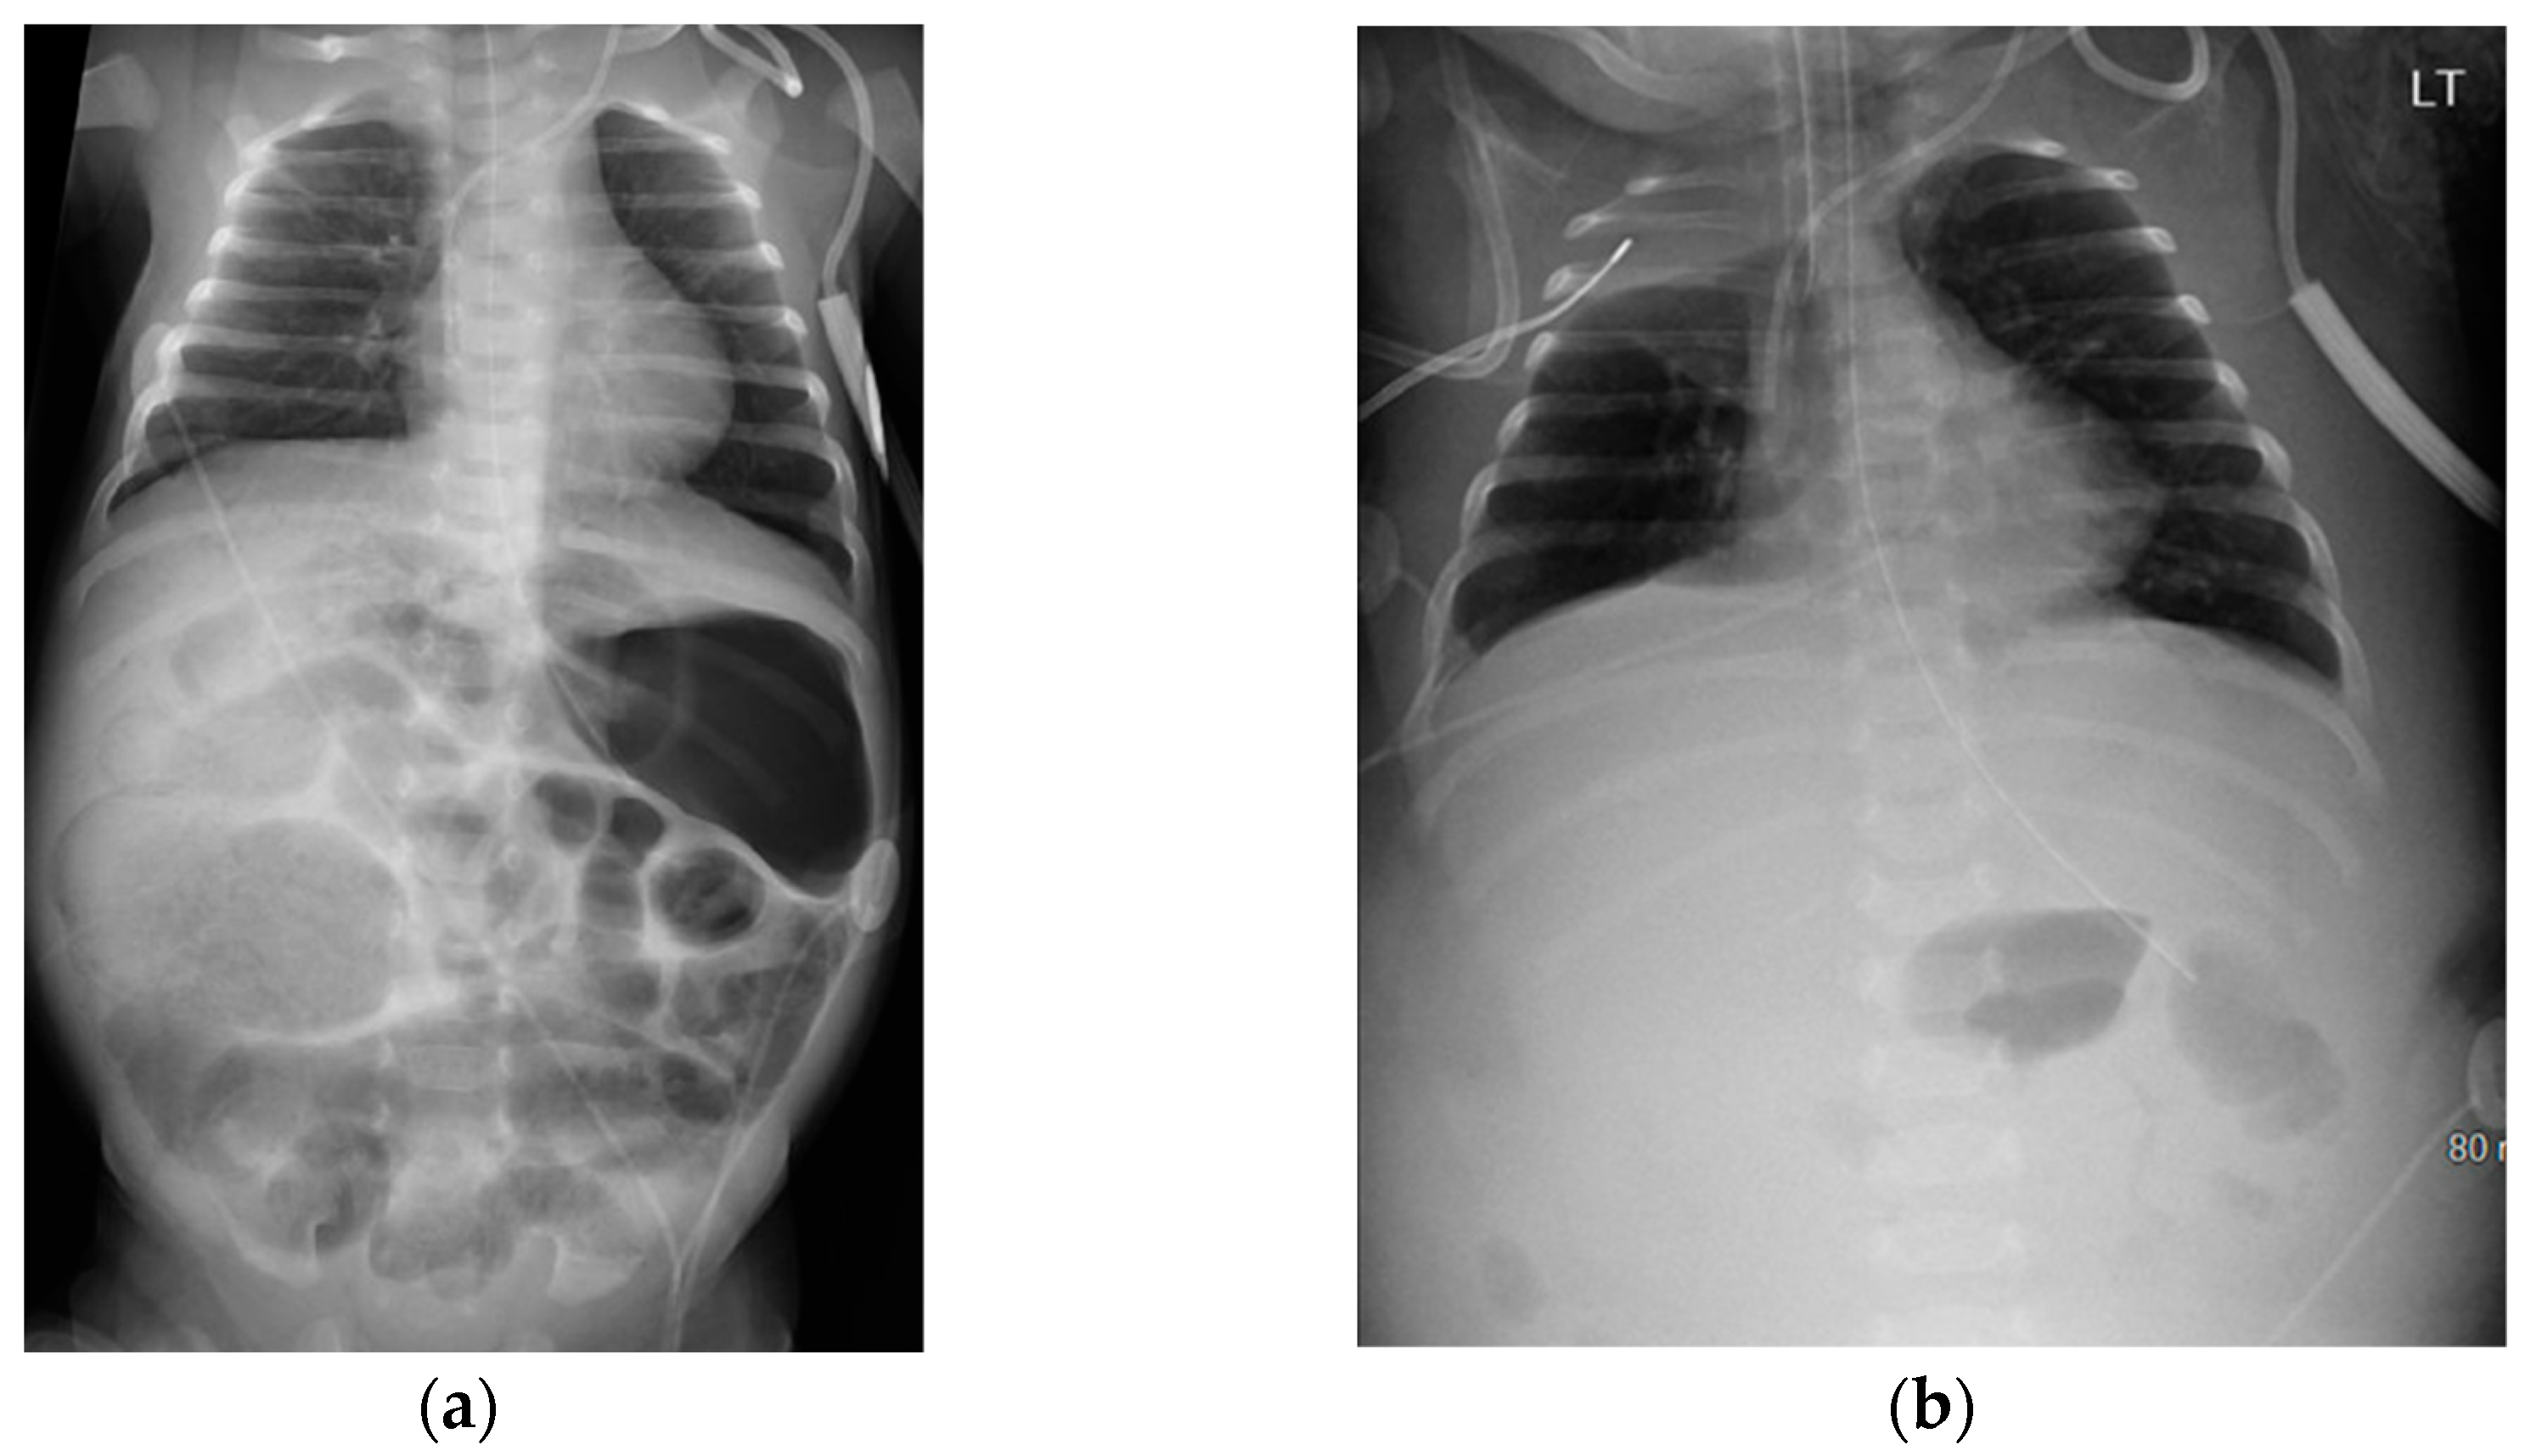

On DOL 41, the infant developed abdominal distension and tenderness, with AXR showing pneumatosis with portal venous gas (Figure 4a), suggesting recurrent NEC later progressing to featureless bowel loops (Figure 4b). The infant developed significant ascites with marked edema along with shock, necessitating a saline bolus, dopamine, multiple transfusions, and antibiotics (Vancomycin, Piperacillin-Tazobactam, and Metronidazole). An exploratory laparotomy on DOL 51 involved abdominal washout, drainage, and temporary closure of perforated intestinal loops. Due to extensive inflammatory phlegmon, double-barrel intestinal stomas were created, and the abdomen was left open for healing and covered with a sterile dressing under a transparent adhesive film, with the repaired loop positioned beneath. Wound cultures from ex-lap grew Klebsiella, leading to a change in antibiotics to Meropenem.

Figure 4. Abdominal X-ray on Day 41 and Day 50 suggesting recurrent necrotizing enterocolitis; (a) Day 41 abdominal X-ray revealing pneumatosis with portal venous gas; (b) Day 50 Abdominal X-ray revealing abdominal distension with featureless bowlet loops.